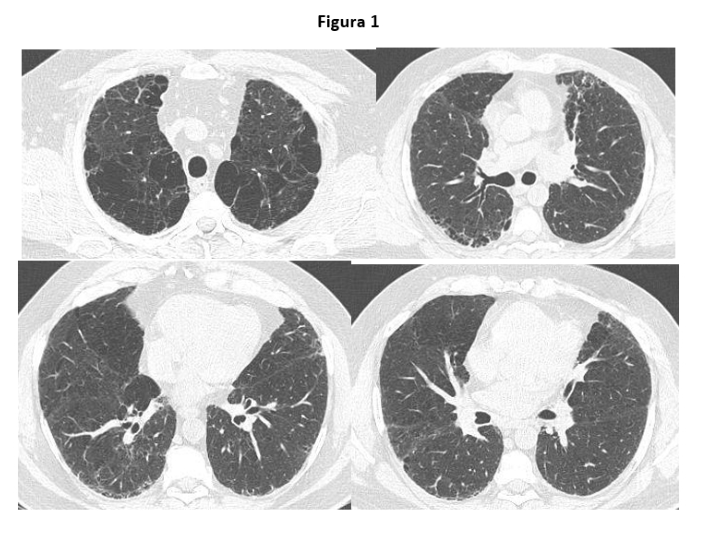

En la tomografía computada de alta resolución (TCAR) se observó la presencia de enfisema centrolobulillar y paraseptal bilateral en lóbulos superiores con reticulaciones en las bases sin signos evidentes de panal de abejas (ver Figura 1).